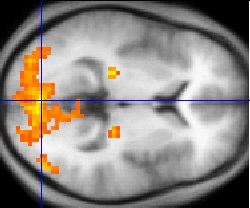

腦成像技術(如 fMRI)與神經電生理學的飛速發展,揭示了所謂「自由意志」與決策,與特定的大腦神經迴路深度相關。利貝特(Benjamin Libet)的經典實驗甚至暗示,大腦在我們「意識到」做出決定之前,就已經開始準備行動。意識逐漸被理解為大腦複雜互動的「湧現屬性」(emergent property),而非一個獨立的「發號施令者」。

3.0 反身回路:能自省與質疑結構

對應腦部:背外側前額葉皮層(Dorsolateral Prefrontal Cortex, DLPFC)、後扣帶皮層(Posterior Cingulate Cortex)、島葉(Insula)

功能對應:DLPFC 是元認知、自我監控、工作記憶的核心腦區;後扣帶與默認模式網絡(DMN, Default Mode Network)相關,負責自我反思。這些功能非常契合「覺察語義錯配、停頓、質疑」的 3.0 回路。